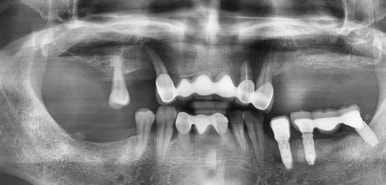

치료전( 앞니 브릿지 떨어져서 덜렁이는 상태, 다른 곳에서 임플란트 찢어져 실패해서 잇몸에 묻혀진 상태)

어금니 타치과에서 실패한 인플란트(찢어져 있어서 임플란트 머리를 올리지 못한 상태)는 제거하고

어금니 빈 곳에 임플란트를 3개 심고 머리는 4개 만들어 어금니 4개 완성

및 앞니부위에는 기존 흔들리고 덜렁거리는 앞니 브릿지 제거하고

썩은 뿌리로 인한 염증치아의 썩은 뿌리만 남은 것 발치 후

앞니용 얇은 임플란트를 식립하였습니다.

네비게이션 임플란트를 사용하여 적절한 간격과 각도를 유지하였고

특히 앞니의 경우 뼈가 매우 얇았으나 내비게이션을 사용하여

뼈가 얇아도 뼈를 뚫고 나갈 위험이 없이 적절한 뼈 위치에 임플란트를 식립하였습니다.

어금니 임플란트 완성 및 임플란트 치료중 사진 (왼) / 완성 후 사진(오른쪽)

어금니 임플란트가 완성된 모습(왼쪽) 및 앞니 임플란트 진행중인 사진과

완성된 사진